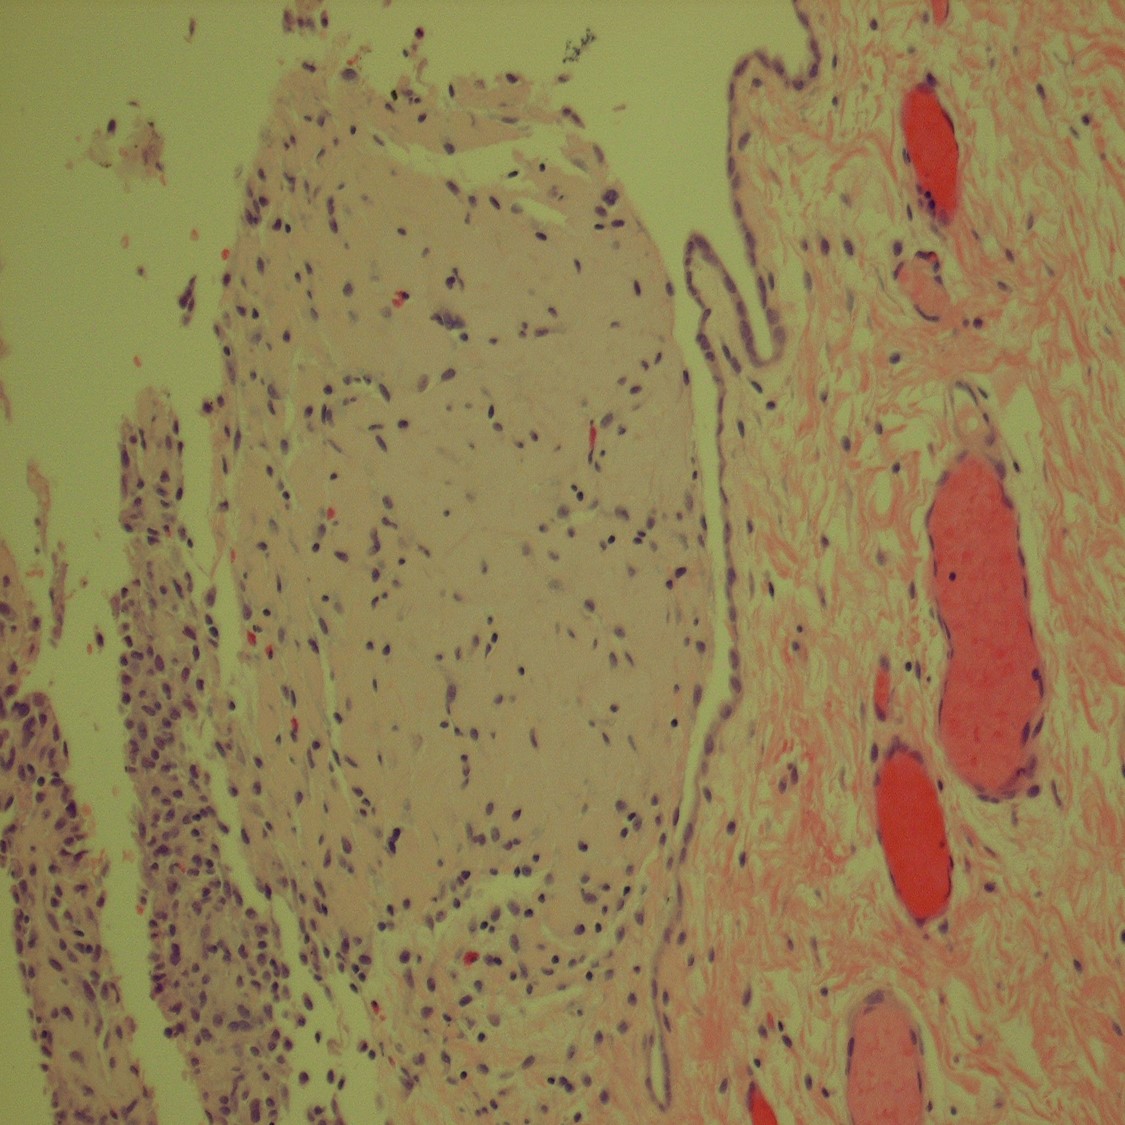

A 28 year old male presents with gross hematuria after a trip abroad. Cystoscopy and...